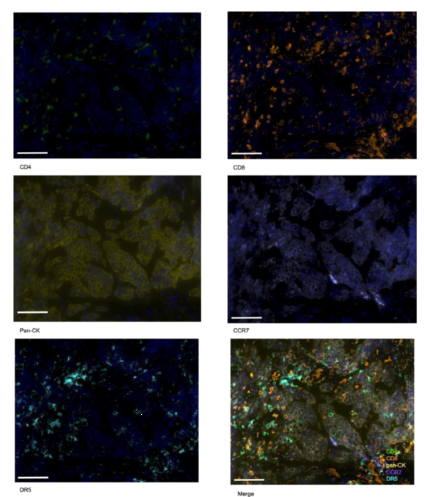

研究通过TissueGnostics的TissueFAXS平台(多光谱成像系统),对肿瘤组织样本进行多重免疫荧光染色与成像分析,核心目标是同时可视化并量化肿瘤微环境中关键免疫细胞及分子的分布与密度。

- 检测靶点覆盖:同步分析CD4+ T细胞、CD8+ T细胞、泛细胞角蛋白(pan-CK,标记肿瘤细胞)、CC趋化因子受体7(CCR7)、死亡受体5(DR5)等5种标志物,明确免疫细胞与肿瘤细胞的空间关系。

- 技术优势:通过光谱分离技术消除自发荧光干扰,*区分不同标志物的特异性信号,实现对复杂微环境中单一细胞群体的*计数与密度量化,为后续关联分析提供可靠数据基础。

TissueGnostics的StrataQuest软件用于图像数据分析,通过统一的阳性判定标准和密度计算方法,确保了35例纳入微环境分析的样本数据具有可比性和重复性;同时,该技术生成的可视化图像(如高/低响应组的免疫细胞分布对比图)也为研究结果提供了直观的形态学证据,增强了结论的可信度。

Figure 10 对高应答患者进行 CD4、CD8、泛细胞角蛋白、趋化因子受体 7 及死亡受体 5 的多重免疫荧光染色